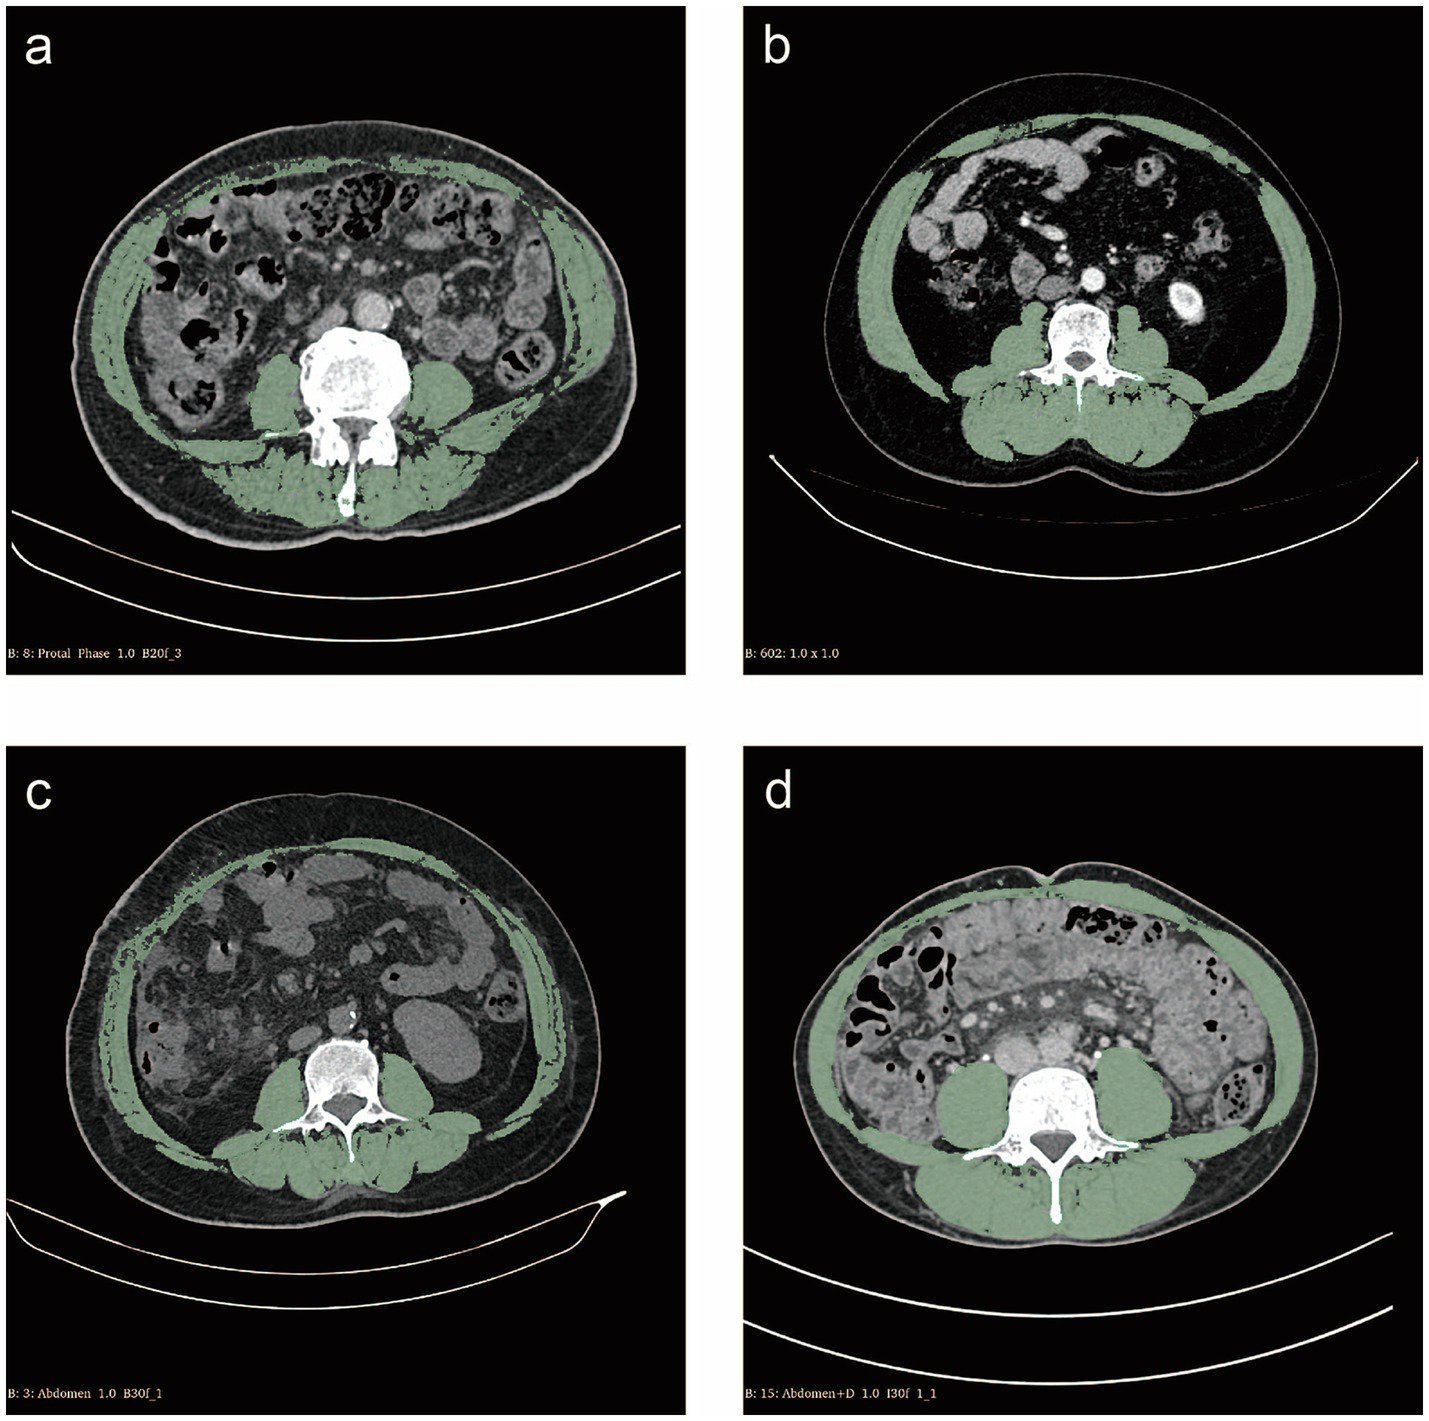

Slice-O-Matic software (version 5.0; Tomovision, Montreal, Canada) was used by two researchers independently in a blinded fashion to identify and quantify skeletal muscle, subcutaneous adipose tissue, visceral adipose tissue and their total cross-sectional area at the L3 level in Hounsfield units (HU). The threshold range was defined as follows: skeletal muscle was defined as −29 HU to 150 HU, subcutaneous adipose tissue was defined as −190 HU to −30 HU, and visceral adipose tissue was defined as −150 HU to −50 HU (Figure 1) (12).

Figure 1. Cross-sectional computed tomography measurement of skeletal muscle areas (green) at the L3 vertebral layer. (a) Patient with sarcopenia of skeletal muscle index (SMI) 38.74 cm2/m2; (b) Patient without sarcopenia of SMI 61.99 cm2/m2; (c) Patient with myosteatosis of skeletal muscle density (SMD) 35.53 HU; (d) Patient without myosteatosis of SMD 56.62 HU.